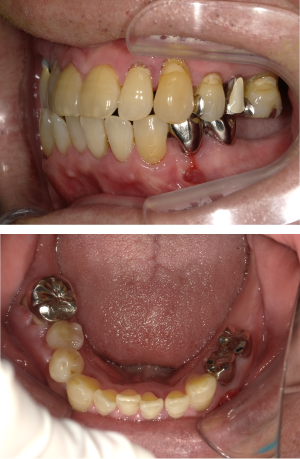

50代 インプラント治療(右上3左上3のみGBR)

| 年代・性別 | 50代・男性 |

|---|---|

| 主訴 | 入れ歯が合わず毎日ヨーグルトしか食べることができないので、しっかり咬めるインプラントにしたい。 |

| 部位 | 右下⑦⑥5④ 上顎③2①①2③ 左下67 |

| 治療期間 | 約9ヶ月 |

| 費用 | ¥4,273,500(税込) |

| 副作用・リスク |

|